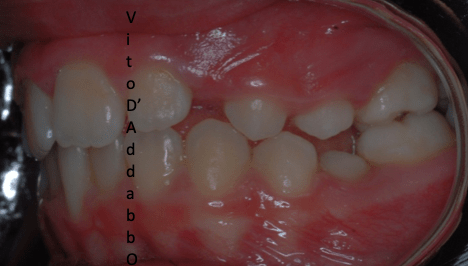

dopo – fase 1